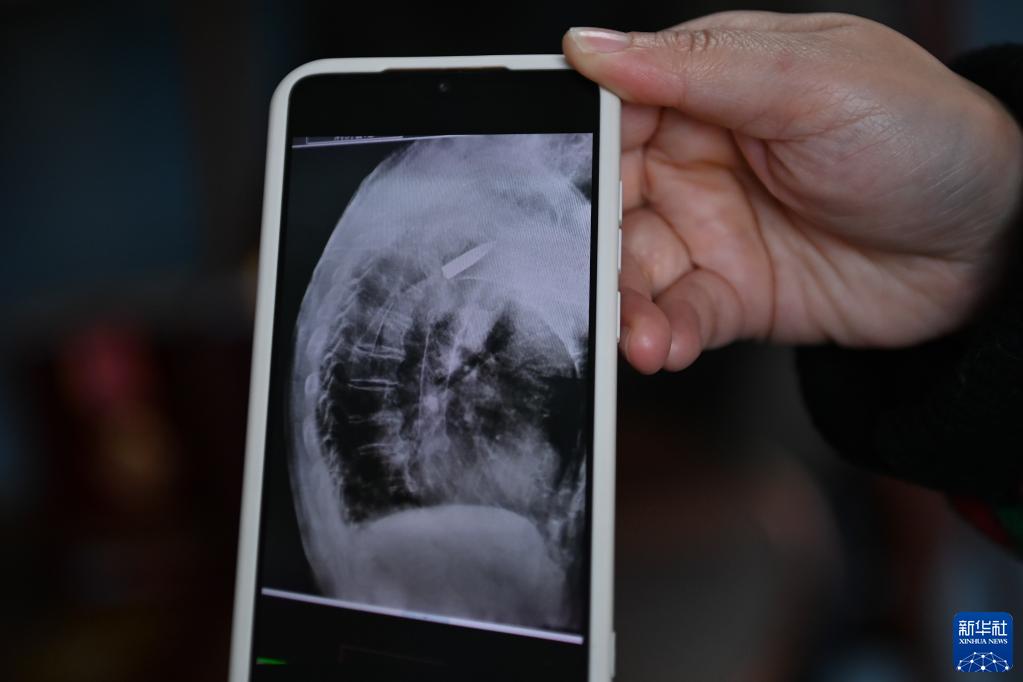

醫院的放射線視覺指引圖像顯示,羅錦文老人右側肩膀里有一顆長約3.5厘米的子彈(3月2日攝)。新華社記者 黃宗治 攝

2022年11月11日上午,浙江省平湖市第一人民醫院,消化科內鏡室主任醫師王明友正在為一位吞咽困難的96歲老人做食道支架置入手術。突然,醫生的眉頭緊皺起來:在X射線下,發現老人右側肩膀里居然有一顆長約3.5厘米的子彈!

2022年,平湖市第一人民醫院在給老人做食道支架置入手術時,X射線下清晰地看到老人肩膀里有顆長約3.5厘米的子彈。而這顆子彈,早已與老人的骨頭粘在了一起,無法取出。